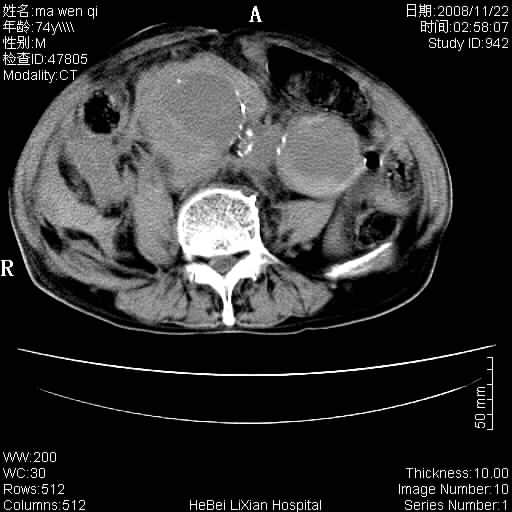

患者男 74岁.突然昏迷,休克6小时.血压70/30,头颅ct未见异常,既往体健.

补充病史,保留导尿10小时,尿袋内只有少许尿液,患者于住院后15小时后去世.

腹主动脉、双侧髂动脉夹层动脉瘤破裂出血进入腹腔。

1)考虑双侧髂动脉瘤并右侧动脉瘤破裂出血,右侧腹膜后及腹腔积血。2)双侧腹股沟疝。

1)考虑,腹主动脉、双侧髂动脉夹层动脉瘤破裂伴右侧腹膜后及腹腔积血。2)双侧腹股沟疝。